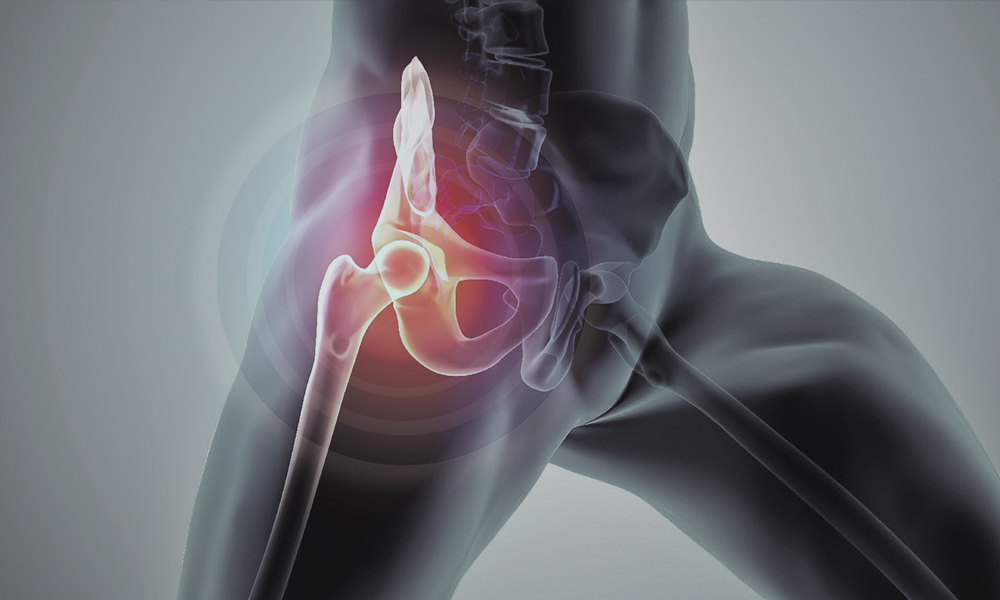

Ορθοπεδική- Μικροχειρουργική

Aκρίβεια, αποκατάσταση, απόδοση

Η συνεχής πρόοδος στην ιατρική τεχνολογία αναβαθμίζει σημαντικά τις δυνατότητες στην Ορθοπεδική και Μικροχειρουργική, προσφέροντας προηγμένα εργαλεία που υποστηρίζουν τους ιατρούς στην παροχή υψηλής ποιότητας φροντίδας.

Στην κατηγορία Ορθοπεδική Χειρουργική και Μικροχειρουργική, συγκεντρώνουμε προηγμένο ιατροτεχνολογικό εξοπλισμό που ανταποκρίνεται στις απαιτήσεις των πιο σύνθετων επεμβάσεων, καλύπτοντας τις ανάγκες τόσο των μυοσκελετικών παθήσεων όσο και των λεπτών μικροχειρουργικών διαδικασιών.

Καινοτόμες Λύσεις για Ορθοπεδική & Μικροχειρουργική

• Μείωση χρόνου επέμβασης για άμεσα και ασφαλέστερα χειρουργικά αποτελέσματα

• Επιτάχυνση αναστόμωσης με τεχνολογία αιχμής

• Ταχύτερη επούλωση με ελαχιστοποίηση της τάσης και αισθητικά βελτιωμένο αποτέλεσμα

• Άμεση ανακούφιση από χρόνιο πόνο